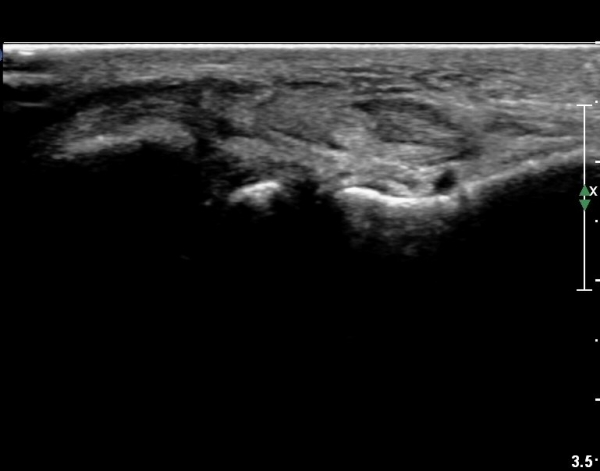

¹ß¸ñ À§¿¡¼­ ¸»´Ü ¾ÕÂÊ °æ°ñºñ°ñÀδë Á¾´Ü¸é°Ë»ç¿¡¼­ ƯÀÌ ¼Ò°ßÀ» º¸ÀÌÁö ¾Ê´Â´Ù(»çÁø 2, 3).